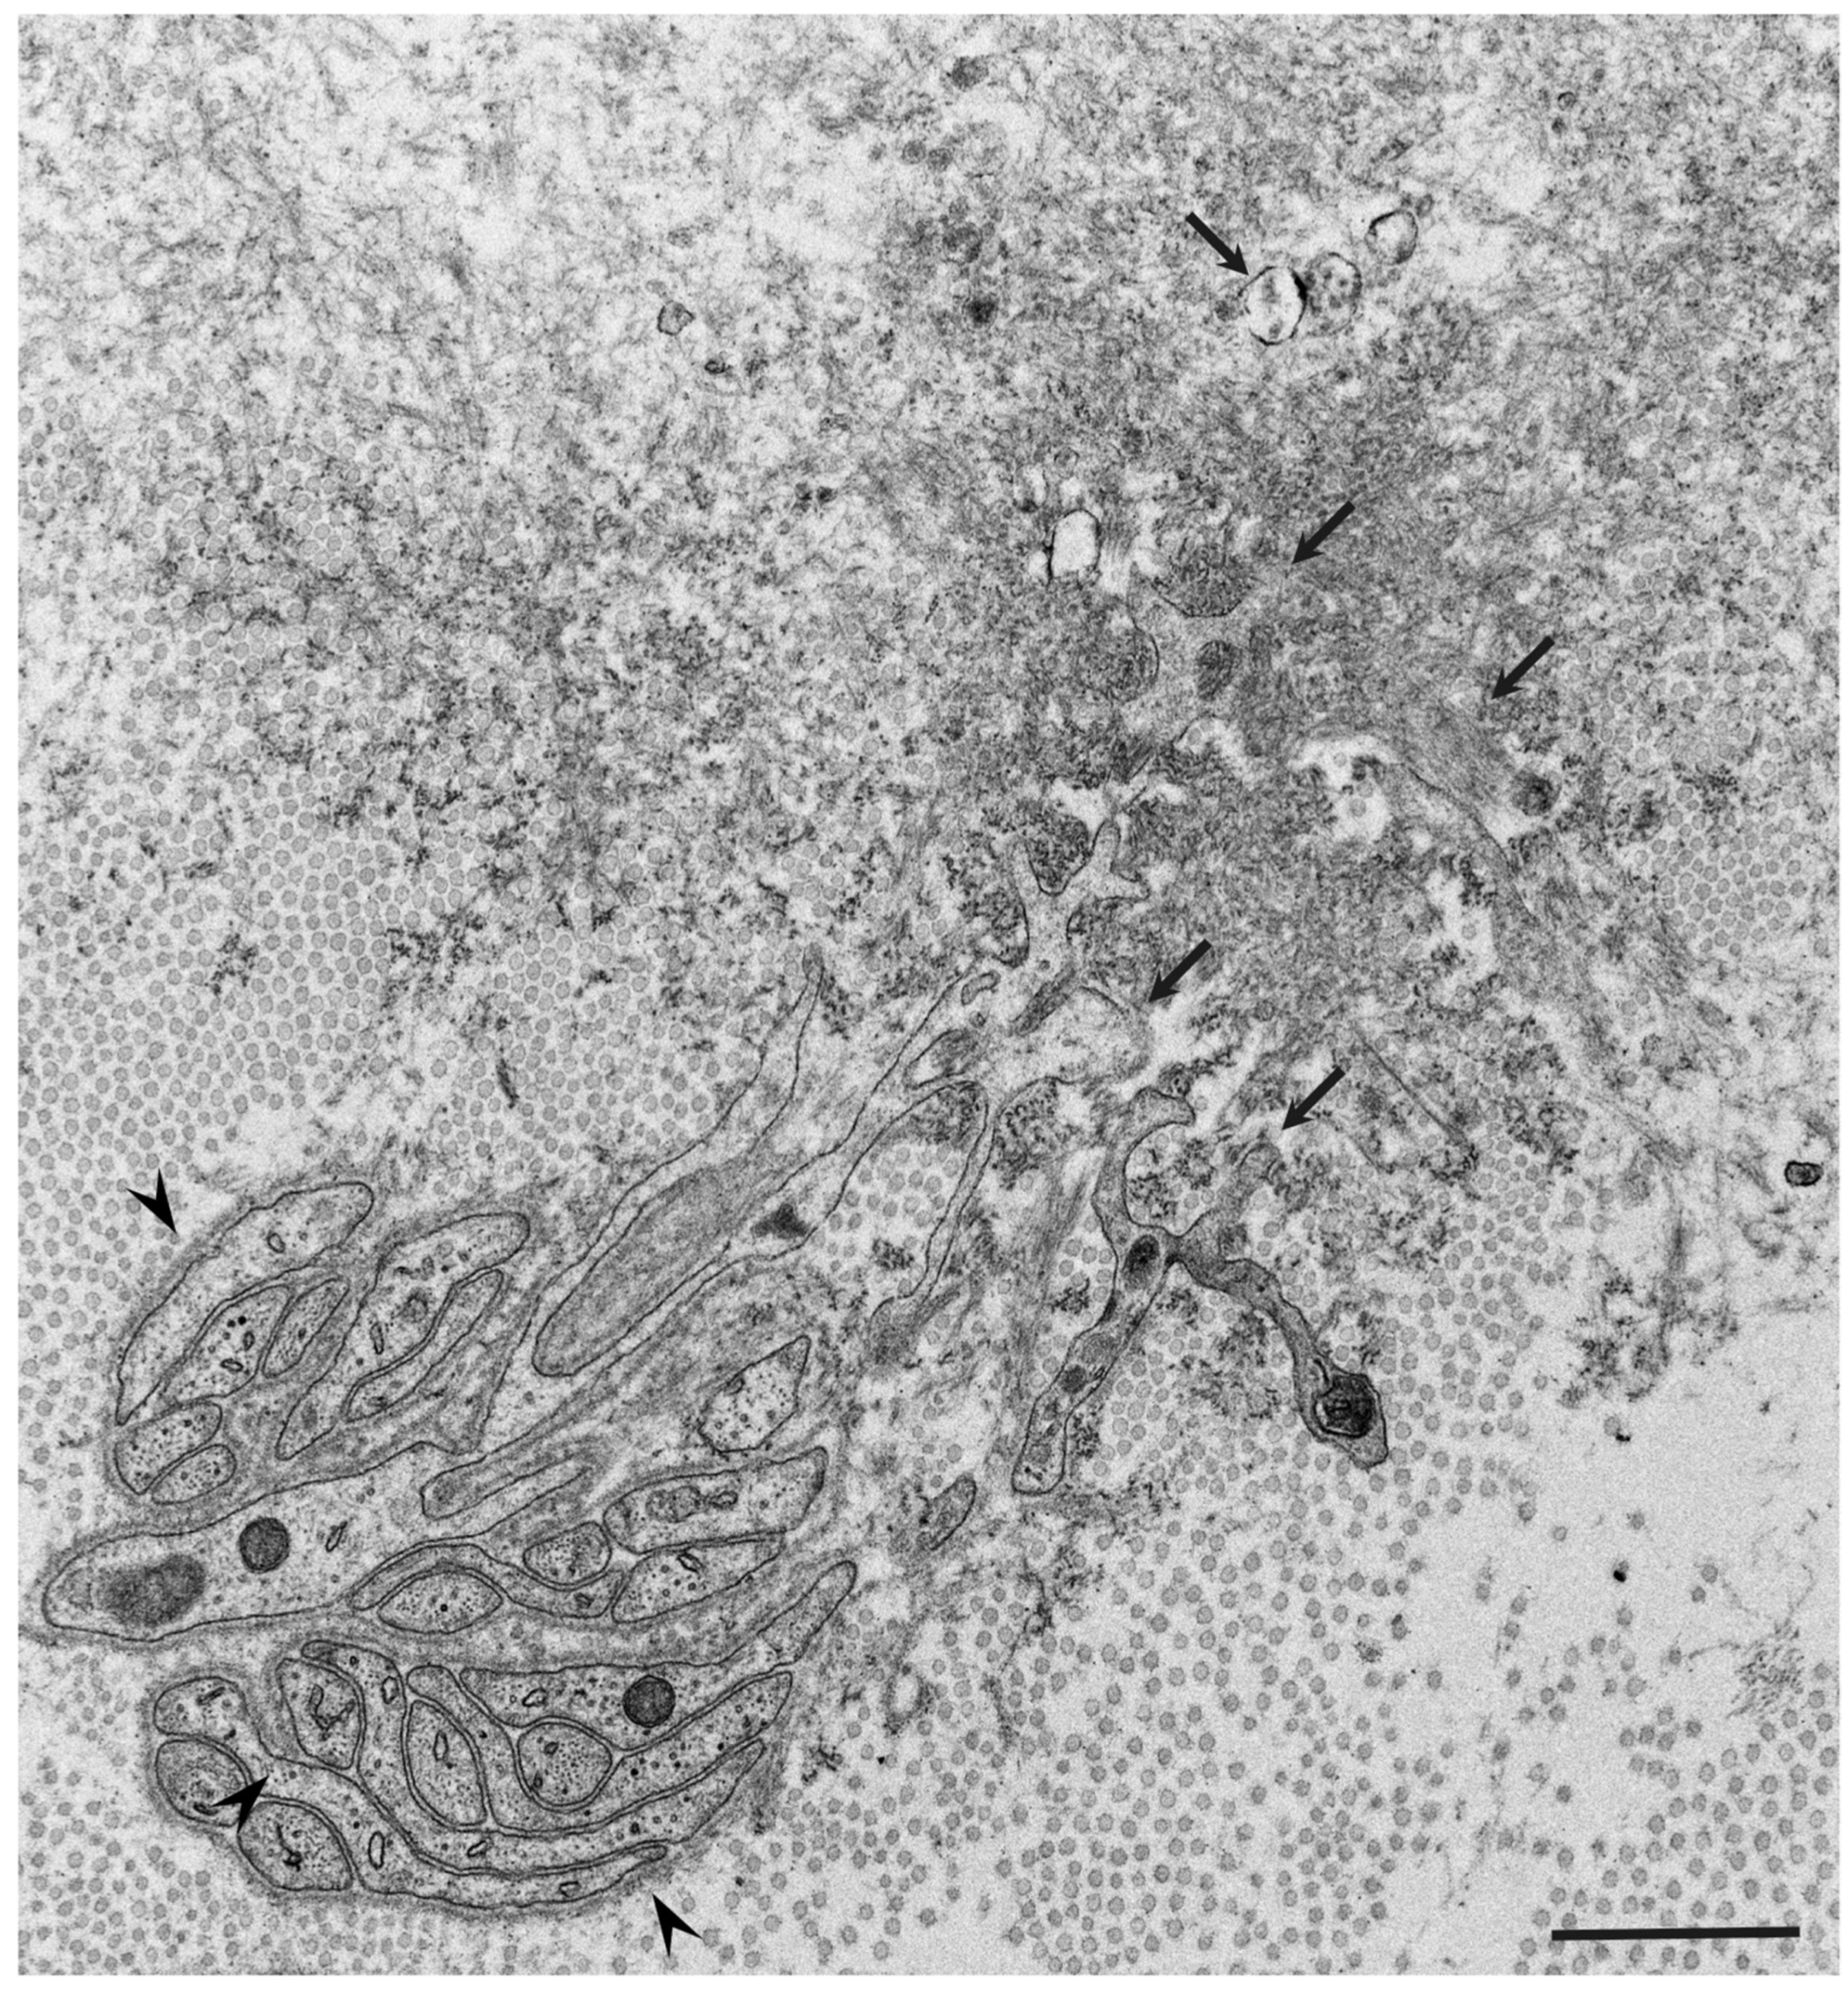

- Koike, H.; Katsuno, M. The Ultrastructure of Tissue Damage by Amyloid Fibrils. Molecules 2021, 26, 4611. [Google Scholar] [CrossRef] [PubMed]

- Koike, H.; Ikeda, S.; Takahashi, M.; Kawagashira, Y.; Iijima, M.; Misumi, Y.; Ando, Y.; Ikeda, S.-I.; Katsuno, M.; Sobue, G. Schwann cell and endothelial cell damage in transthyretin familial amyloid polyneuropathy. Neurology 2016, 87, 2220–2229. [Google Scholar] [CrossRef]

- Koike, H.; Nishi, R.; Ikeda, S.; Kawagashira, Y.; Iijima, M.; Sakurai, T.; Shimohata, T.; Katsuno, M.; Sobue, G. The morphology of amyloid fibrils and their impact on tissue damage in hereditary transthyretin amyloidosis: An ultrastructural study. J. Neurol. Sci. 2018, 394, 99–106. [Google Scholar] [CrossRef] [PubMed]

- Koike, H.; Mouri, N.; Fukami, Y.; Iijima, M.; Matsuo, K.; Yagi, N.; Saito, A.; Nakamura, H.; Takahashi, K.; Nakae, Y.; et al. Two distinct mechanisms of neuropathy in immunoglobulin light chain (AL) amyloidosis. J. Neurol. Sci. 2021, 421, 117305. [Google Scholar] [CrossRef] [PubMed]